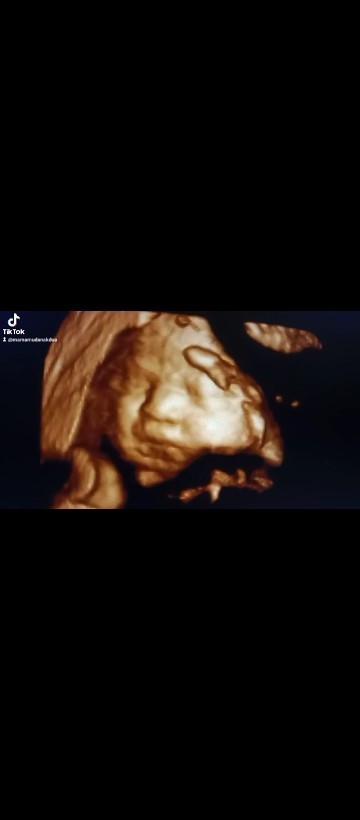

Usg 4d 29-30minggu

Alhamdulillah kemaren sudah usg 4d ini bunda2.. Kenalinn ini gadis cantikku..anak ke 4 Bbj 1,575kg Minta doanya ya bunda2 semua semoga d beri kelancaran sampe persalinan nanti. Dan semoga bunda2 semua juga sehat2 bersama calon bayi tercinta..